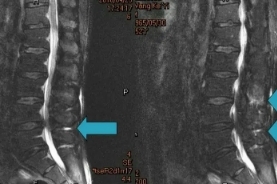

4、手术治疗,对各种非手术治疗无效的病例,可施行手术治疗.

5、激光针刀松解术